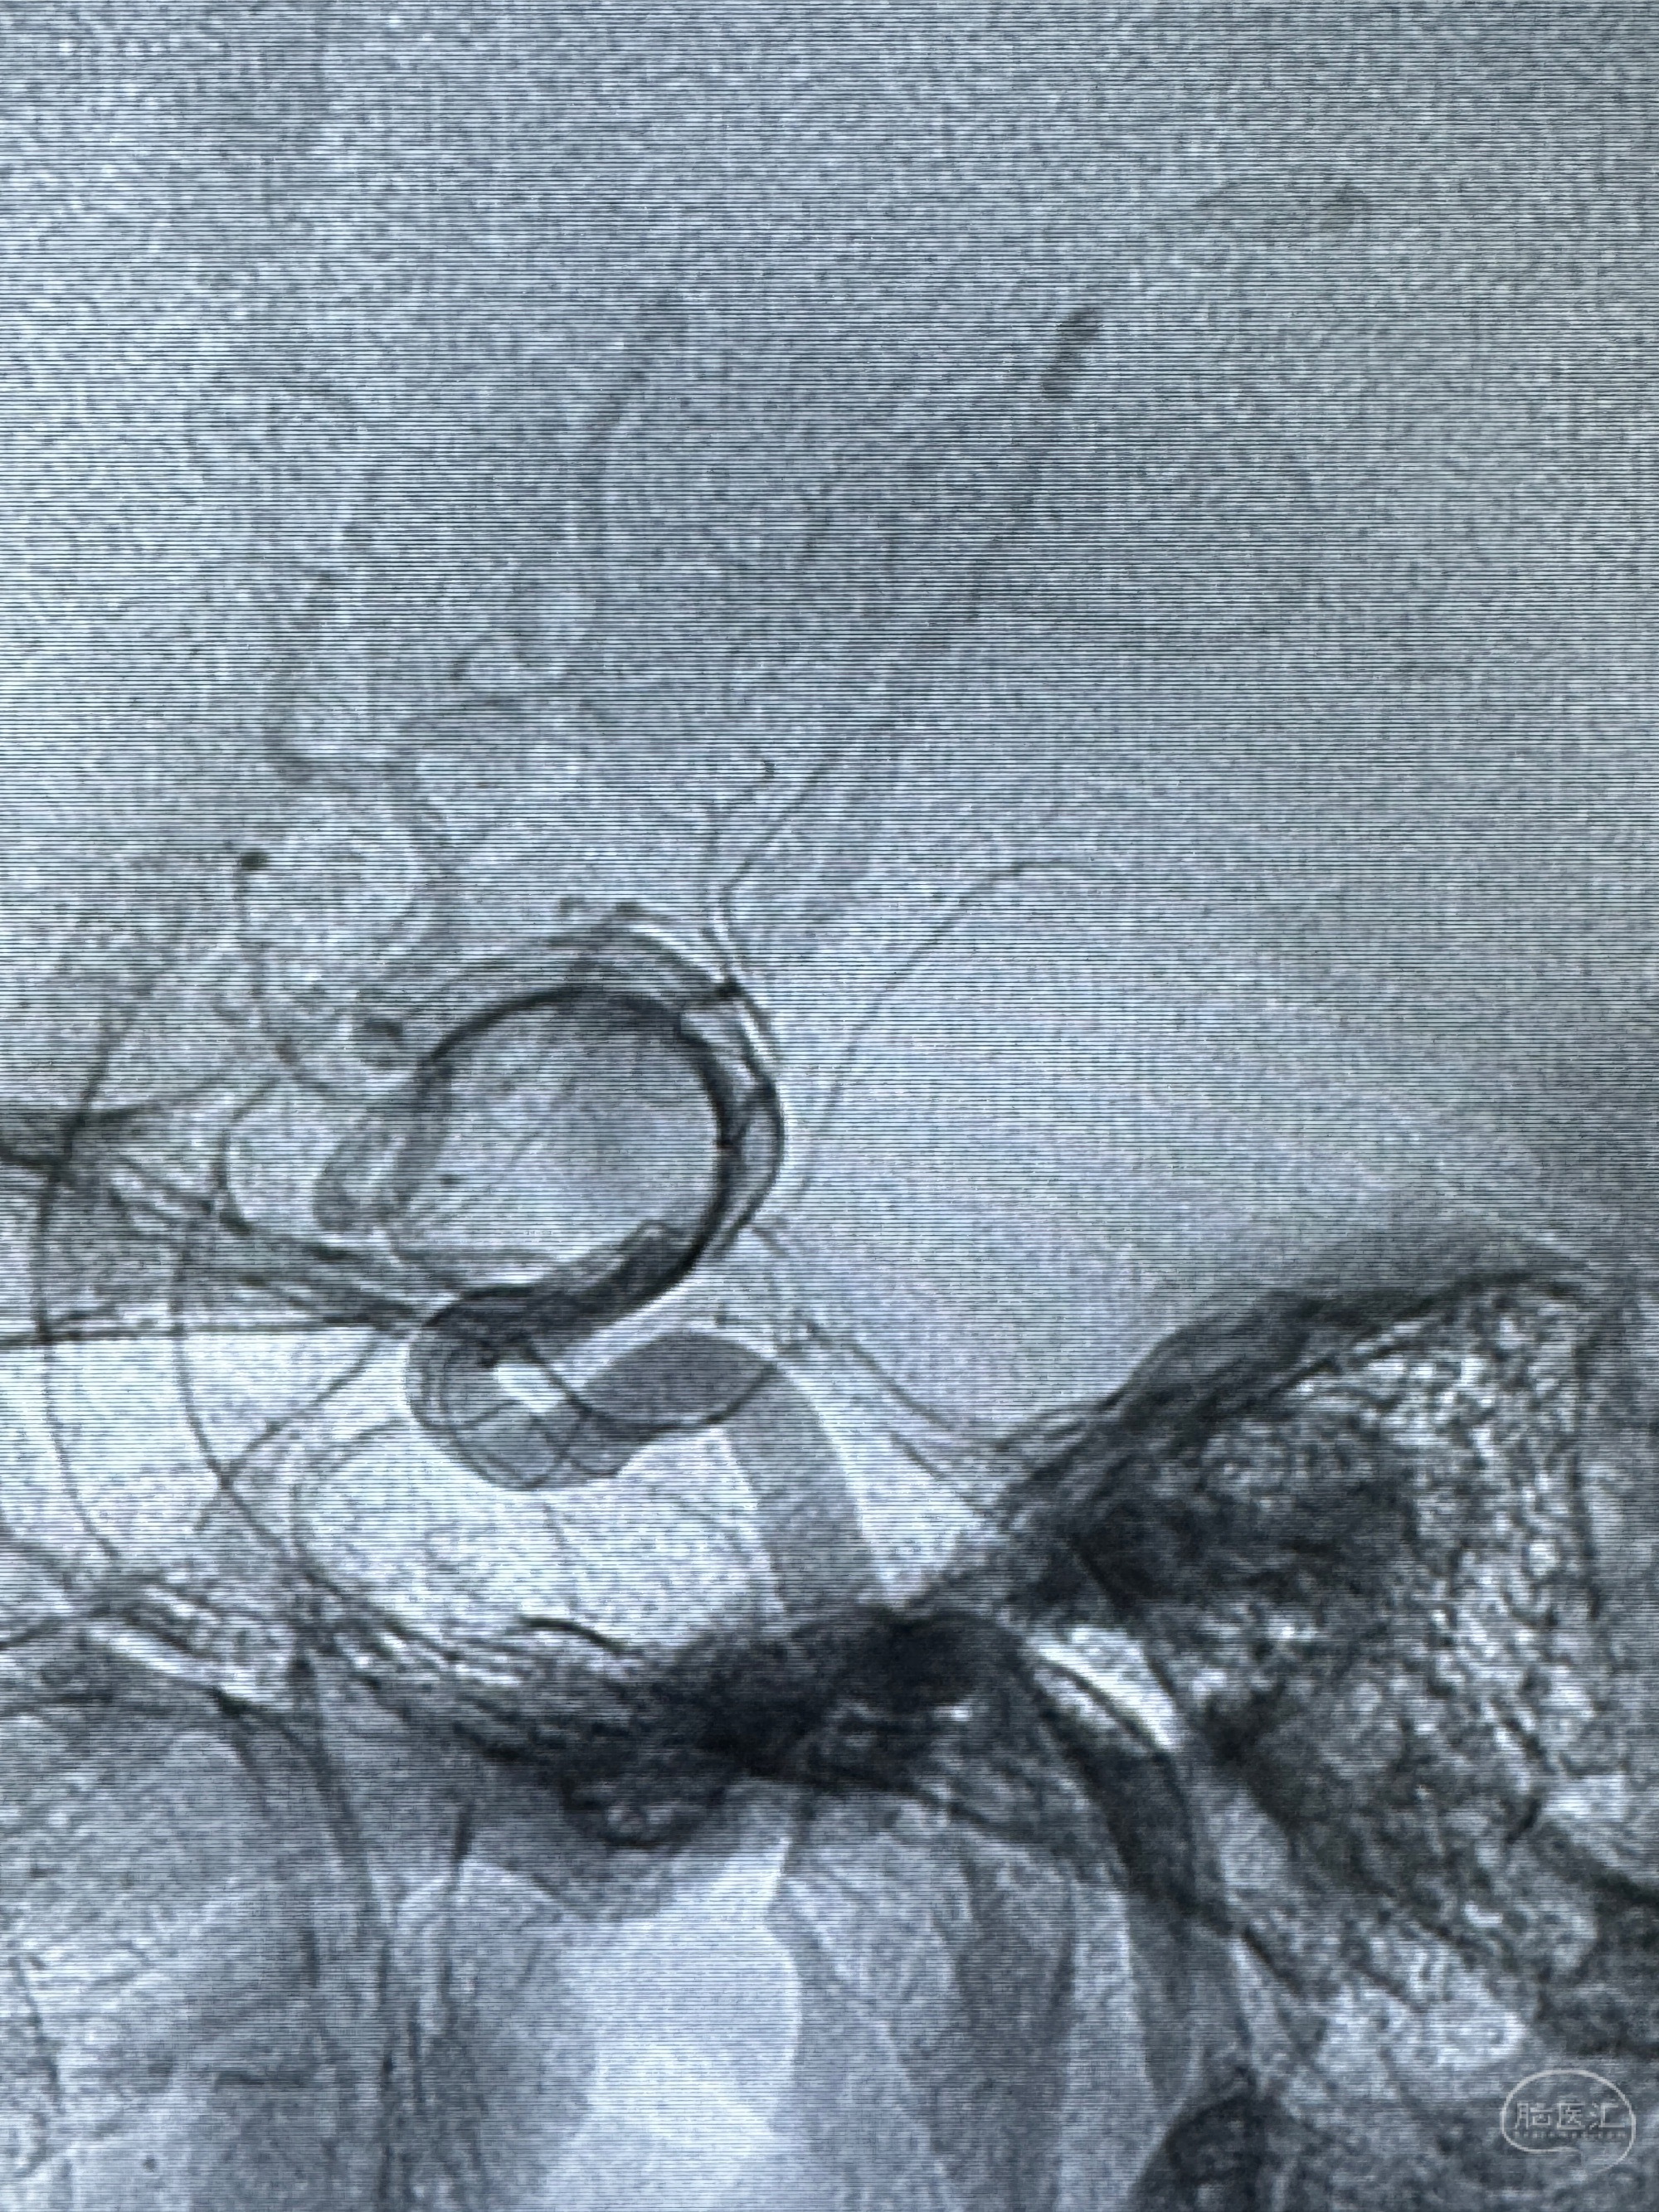

透视可见红圈部分为支架导管的头端

手推冒烟显示支架位置及展开情况,箭头为支架导管的位置

尝试回收支架失败,只能考虑释放支架了

逐帧图像展示歪着脖子释放支架,旁边吩咐助手手机摄影、拍照留像(透视机不能留影像)